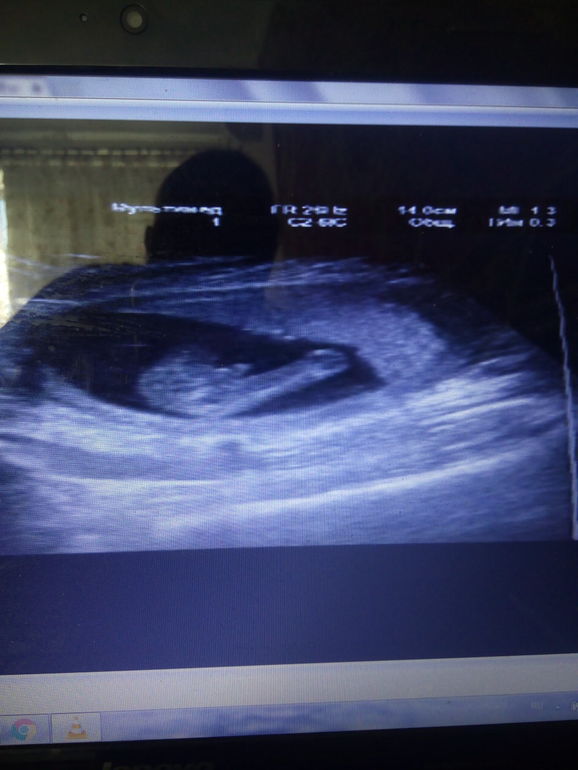

была сегодня на УЗИ;)))))это такое счастье и удивление и страх и все в одном флаконе!

тайна наша раскрыта........и у нас......замечательный мальчик

по малышику:

срок по М 15+2,

по развитию плода-15+6

вес 130г

чсс 169

теперь обо мне :гипертонус миометрия стойкий по передней стенке

положения плода :косое,головка справа внизу.

Вот собственно и все))))растет мой мальчик

Видела да и мне видео на диск записали;))) вот фото из видео причендала😂😂😂😂 удачи на узи 😘😘😘